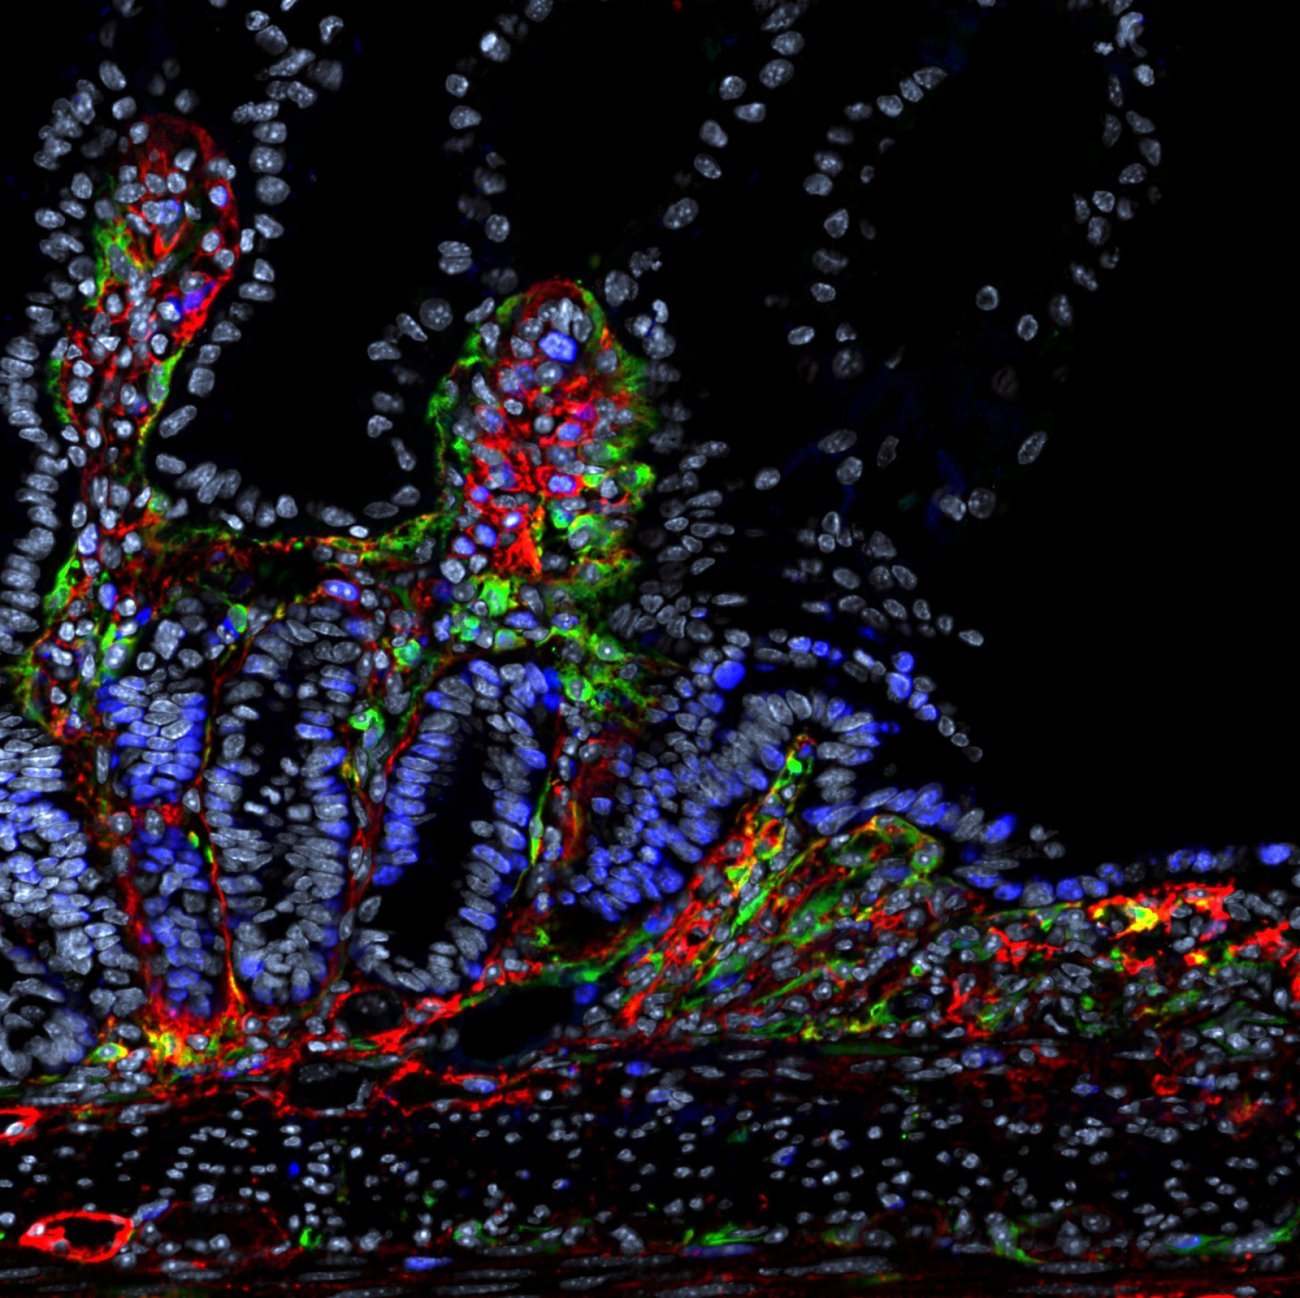

Notre système immunitaire n’est pas statique : il évolue tout au long de la vie, façonné par des facteurs comme l’âge, le sexe ou l’histoire vaccinale. Grâce à des technologies de pointe comme le single-cell sequencing, ces variations peuvent être analysées, révélant les mécanismes du déclin immunitaire lié à l’âge.

Le séquençage de cellule unique (single-cell sequencing) est une technologie de pointe analysant l’ARN cellule par cellule, révélant leur diversité et leur fonctionnement individuel. Grâce à des systèmes microfluidiques, elle identifie des sous-populations cellulaires – comme des cellules tumorales résistantes aux traitements – ou des sous-populations rares apparaissant avec l’âge indétectables par les méthodes classiques. En oncologie, elle permet de distinguer les cellules saines des cellules malignes et d’affiner les cibles thérapeutiques. Cette approche révolutionne les diagnostics, les traitements personnalisés et la compréhension des maladies.

En exposant in vitro les cellules sanguines de 380 individus de la cohorte “Milieu Intérieur” à des pathogènes comme le SARS-CoV-2 ou le virus de la grippe, il a été démontré que les personnes âgées présentent une réponse immunitaire affaiblie, notamment en raison d’une production réduite d’interféron alpha, une protéine cruciale pour bloquer la réplication virale. « Parallèlement, l’analyse de l’ensemble des gènes montre que les lymphocytes T CD4 sont le type cellulaire le plus impacté par l’âge », complète le chercheur.